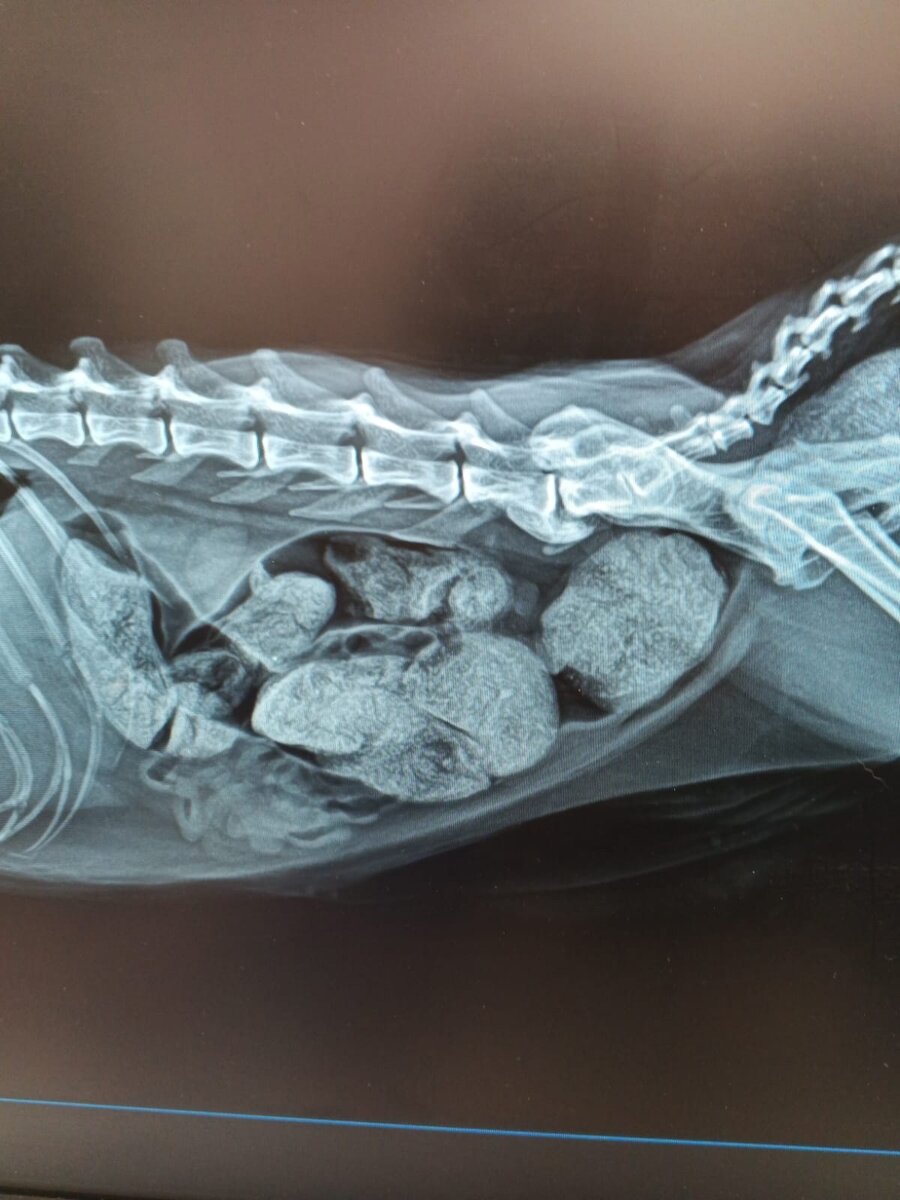

Для наглядности прилагаю рентгеновские снимки кошки, которая не испражнялась 7 дней.

Как видите, кишечник полностью забит довольно большим объемом каловых масс.

Благодаря этому питомец естественным образом теряет аппетит, жизненную энергию и страдает от интоксикации организма.

Надо ли говорить, что подобное состояние может закончиться мучительной гибелью?

В данном случае постановка клизмы, размывание каловых масс и прочие стандартные процедуры будут абсолютно не эффективны.

Помочь может только хирургическое извлечение скопившихся масс, а также последующее лечение в сочетании с грамотной диетой, которая позволит восстановить функции кишечника.